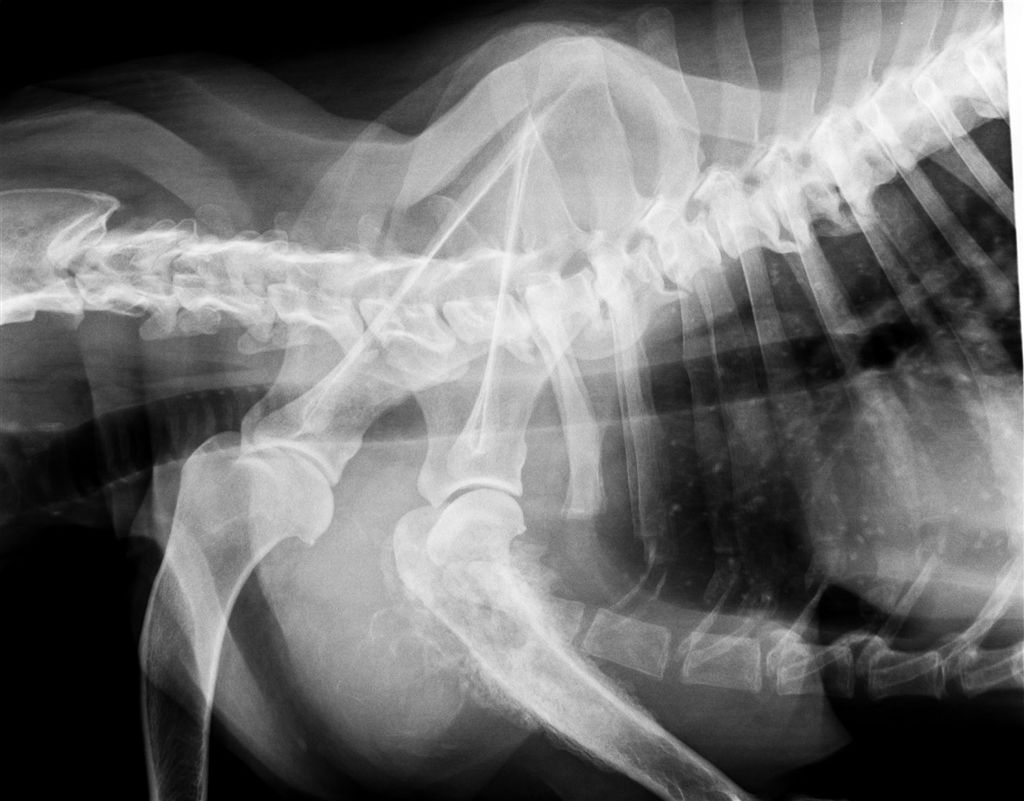

トイプードル 4.5才 メス BW3.3kg

左前足を上げている

抱き上げようとしたら痛がった

首に力入っている 下に動かさない

触ると痛がる

軽度の冠軸亜脱臼